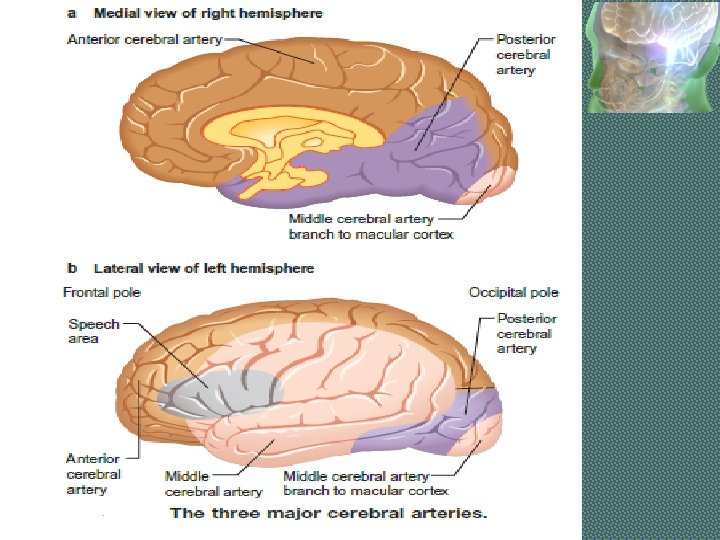

MIDDLE CEREBRAL ARTERY • Supplies lateral surface of frontal, perital and temporal lobes • Most of the motor and sensory cortex Ecxept the part on medial side and control lower limb, internal capsule Total Occlusion: • Uncrossed hemiplegia • Hemianesthesia • Global Dysphasia • Homonymous hemianopia • Apraxia, Agnosia Partial occlusion: • Any of the above features. • Lower limb is either not or minimally involved

ANTERIOR CEREBRAL ARTERY • Supplies MEDIAL surface of hemisphere • Motor and sensory cortex on medial side which control lower limb • Soon its origin it gives a penetrating branch (Heubner’s artery) which supply internal capsule (containing fibers of upper limb and face) Occlusion at the origin: Features are similar to total occlusion of MCB Occlusion of Heubner’s artery : • Weakness of upper limb and face Occlusion after the origin of Heubner’s artery : • Weakness of lower limb • Loss of cortical sensory function in lower limb

POSTERIOR CEREBRAL ARTERY • Branch of Basilar artery • Supplies occipital lobe which include visual cortex Occlusion: • • Visual field loss Homonymous hemianopia Visual agnosia Disorders of reading Disorders of color vision Memory impairment Motor dysfunction